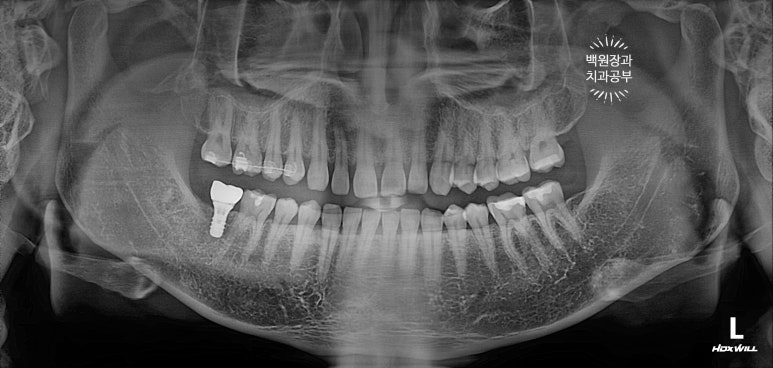

보철물 완성 후 촬영한 치과용 파노라마 사진입니다.

보시면 부분 교정 치료 후 오른쪽 위 두번째 큰어금니는 함입되어 제 자리로 돌아갈 수 있었고,

덕분에 추가로 삭제할 필요 없이, 아래 임플란트를 온전하게 제작할 수 있었어요.

Before & After!!

뿌리만 남은 오른쪽 아래 두번째 큰어금니와 오른쪽 위아래 사랑니를 발치했고,

약 5개월의 부분교정을 통해 내려와있던 오른쪽 위 두번째 큰어금니를 제자리로 올려주었습니다.

그리고 스트라우만 임플란트로 오른쪽 아래 두번째 큰어금니의 기능을 회복시켜주었어요.

아주 이상적이고 교과서적인 치료라고 생각합니다.

억울한 신경치료를 피함으로써 오른쪽 위 두번째 큰어금니의 생명을 지킬 수 있었어요.